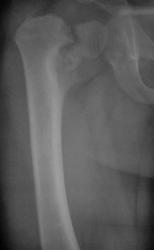

В представленном случае, по всей видимости, имеет место застарелый перелом со смещением отломков, в результате чего и произошло уменьшение шеечно-диафизарного угла.

Нет, травмы в данном случае не было. Имеет место дистрофическая coxa vara, вероятнее всего, врождённаяю. Эпифизеолиз головки, который мы видим на снимке, как мы считаем, наступил вследствие нарушений биомеханики в суставе - ШДУ практически 90 градусов. Добавлю, что факт травмы родители категорически отрицают. Ребёнок постепенно начал хромать, хромата усиливалась на протяжении 6 месяцев.